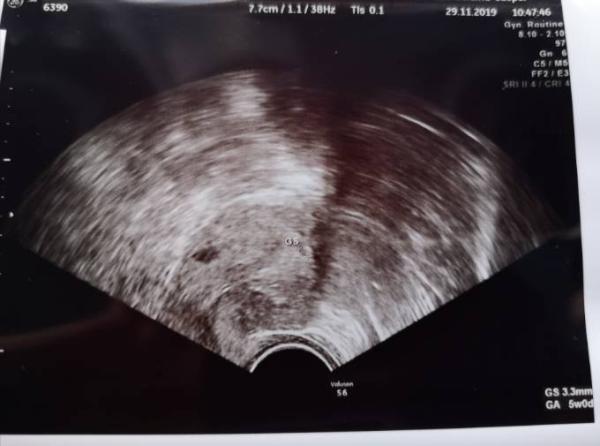

Hallo ihr Lieben, jetzt hab ich mich hier auch mal angemeldet. Lese schon seit Jahren hier Beiträge Wir sind endlich schwanger nach 5,5 Jahren. PU+14... HCG 52 PU+18... HCG 245 Gestern an 5+1 (PU+22) hatte ich einen US. Blut wollte ich mir erstmal nicht abnehmen lassen, weil mich das beim letzten Mal mit der Warterei so fertig gemacht hat. Ich war dermaßen angespannt. Im US konnte die FÄ leider nur eine FH erahnen (da wo GS mit den Kreuzen ist). Das links ist keine FH sondern wohl ein Myom. An 5+6 soll ich wiederkommen. Puh, ich hatte schon etwas gehofft, dass man bei 5+1 eine FH sieht. Wie war das bei euch?

Bild zu 5+1 Ultraschall - Forum für Juli - Mamis